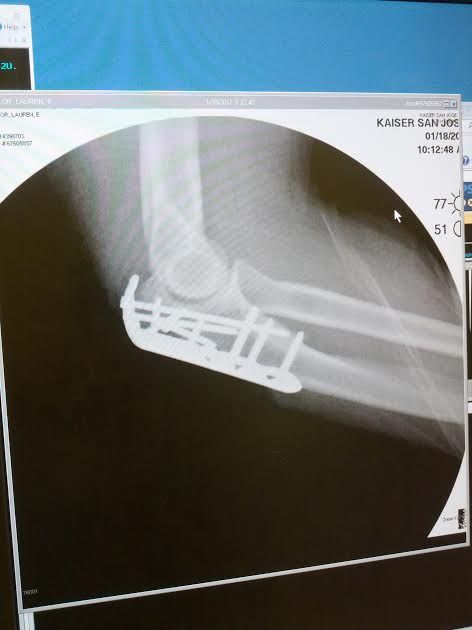

"I knew something was unusual, because my arm hurt more than it should. I've taken plenty of spills, but I was like ooooh, this really aches!" A good Samaritan helped her retrieve her bike and some nearby police came over. They put a safety cone in the pot hole to make sure nobody else hit it. And Sailor was off to the hospital. On Jan. 18 she had surgery and had a titanium plate and screws put into her arm.